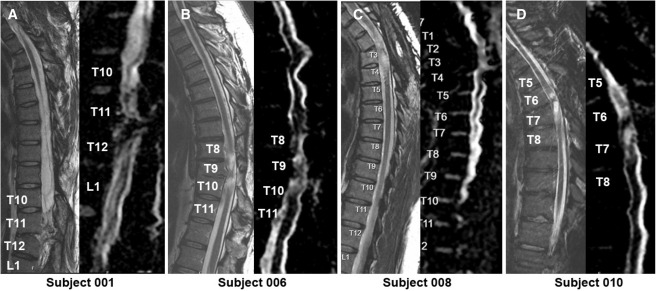

本次發(fā)布的I期臨床研究旨在評(píng)估神經(jīng)干細(xì)胞移植治療慢性胸椎脊髓損傷的安全性和初步療效。研究選取了四名完全性ASIA-A級(jí)胸部SCI患者作為受試者,這些患者的損傷時(shí)間均超過(guò)一年,且在接受任何其他形式的有效治療后仍未見(jiàn)明顯好轉(zhuǎn)。

每位受試者接受了每個(gè)注射點(diǎn)含有2×105個(gè)神經(jīng)干細(xì)胞,通過(guò)定制的立體定向設(shè)備,雙側(cè)注入損傷部位周圍的剩余組織及下方約一個(gè)節(jié)段的內(nèi)側(cè)白質(zhì)區(qū),整個(gè)過(guò)程由術(shù)中熒光透視成像指導(dǎo)完成。

4.影像學(xué)評(píng)估:術(shù)后MRI顯示所有患者存在不同程度的局灶性脊髓軟化,但未見(jiàn)新的并發(fā)影像學(xué)征象(如水腫、增強(qiáng)或積液);DTI提示脊髓束外觀穩(wěn)定,未見(jiàn)廣泛重塑或纖維束改善。